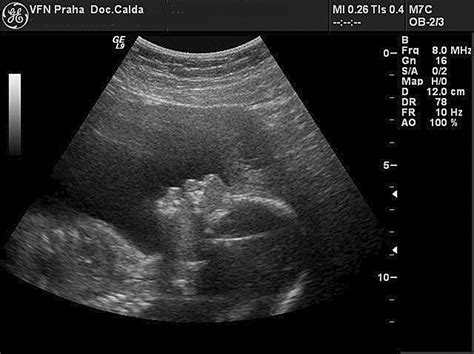

Placenta Grade 3 v 32. týždni tehotenstva: Čo to znamená pre vás a vaše dieťa?

Oznámenie od lekára o "grade 3" placente počas ultrazvuku v 32. týždni tehotenstva môže vyvolať obavy, najmä ak už máte za sebou skúsenosti s komplikovanými tehotenstvami alebo potratmi. Je pochopiteľné, že sa pýtate, či toto zistenie ohrozí úspešný priebeh tehotenstva a či je potrebné špeciálne sledovanie. Táto situácia, hoci nie úplne bežná, nie je dôvodom na paniku, ale vyžaduje si podrobné pochopenie a zodpovedný prístup.

Zrelosť placenty sa hodnotí pomocou ultrazvuku a klasifikuje sa do rôznych stupňov, od Grade 0 do Grade 3. Tento grading odráža štrukturálne zmeny, ktoré placenta podstupuje počas tehotenstva, aby sa prispôsobila rastúcim potrebám plodu.

- Grade 3: Placenta je zrelá, s výraznými kalcifikáciami, ktoré môžu zasahovať hlbšie do štruktúry. Môžu sa objaviť aj oblasti odumretého tkaniva (infarkty). Tento stupeň naznačuje, že placenta dosiahla maximálnu funkčnosť a začína sa jej postupný útlm.

Váš lekár uviedol, že placenta zodpovedá "grade 3" a ultrazvukovo koresponduje s 33. týždňom tehotenstva, aj keď ste v 32. týždni. To znamená, že placenta je zrelšia, než by sa v tomto štádiu bežne očakávalo. Zatiaľ čo placenta Grade 3 je normálnym nálezom v neskorších fázach tehotenstva (často okolo 36. týždňa a neskôr), jej výskyt v 32. týždni môže vyžadovať bližšie sledovanie.